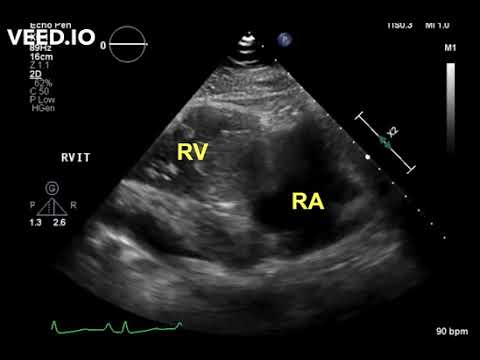

Large Right Atrial Myxoma Presenting As Bilateral Pulmonary Embolism

Unusual Location of a Cardiac Papillary Fibroelastoma

Atrial Myxoma in Echocardiography || Dr. Shankar Dey